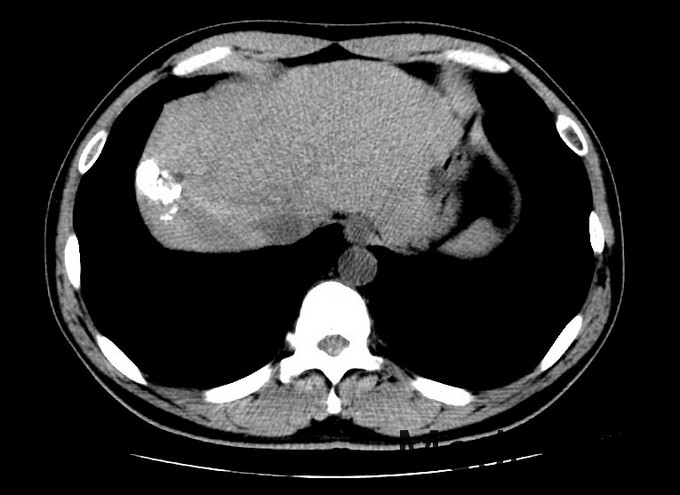

查体:血压131/76mmHg.神志清晰。颜色正常,无皮疹及瘀点。无肝掌。浅表淋巴结未触及肿大。眼睑无水肿,巩膜无黄染,结膜正常。双侧瞳孔等大正圆。心肺听诊无异常。腹型平坦,无腹壁静脉曲张,未见胃肠型及蠕动波,无瘢痕,脐部正常。腹软,无压痛及反跳痛,无腹肌紧张,未触及包块。肝未触及,Murphy征阴性,脾未触及,无触痛,肾未触及。无肝区叩击痛,肝上界位于右锁中线第6肋间,无肾区叩击痛,无脾区叩击痛。移动性浊音阴性。四肢活动自如,无双下肢水肿。扑翼样震颤阴性。 化验:血细胞分析:白细胞计数 3.9 10^9/L、血小板计数 121.0 10^9/L、血红蛋白 134 g/L,肝功酶谱:丙氨酸氨基转移酶 50 U/L、总蛋白 73.5 g/L、白蛋白 42.4 g/L、总胆红素 13.3 umol/L,凝血五项:凝血酶原百分活动度 76.4 %,丙肝抗体 27.90 S/CO,丙肝病毒RNA定量 <1.0E+03 IU/ml,甲胎蛋白 1296.00 ng/mL, 肝脏增强CT示:肝硬化,脾大,腹水少量。肝癌介入手术治疗后,S8段强化灶。肝右叶灌注异常,考虑门脉右前支受侵。

诊断:1丙肝肝硬化 活动期 代偿期 HCC术后 2高血压 治疗:入院后休息,低脂低盐软食。肿瘤辅助治疗,静点苦参碱。抗病毒,口服daclatasvir和sofosbuvir联合利巴韦林。控制血压,口服替米沙坦抗纤维化。对于S8段强化灶,考虑疾病进展,再行TACE治疗。

术后:查体:眼睑无水肿,巩膜无黄染。心肺听诊无异常。腹软,无压痛及反跳痛,无腹肌紧张,未触及包块。肝未触及,Murphy征阴性,脾未触及,无触痛,肾未触及。无肝区叩击痛,无肾区叩击痛,无脾区叩击痛。移动性浊音阴性。 化验:血细胞分析:白细胞计数 8.8 10^9/L、红细胞计数 4.04 10^12/L、血小板计数 113.0 10^9/L、血红蛋白 131 g/L、中性粒细胞百分比 88.4 %,肝功酶谱:丙氨酸氨基转移酶 258 U/L、天门冬氨酸氨基转移酶 245 U/L、白蛋白 34.1 g/L、总胆红素 29.4 umol/L,凝血五项:凝血酶原时间 12.2 秒,C反应蛋白测定:C反应蛋白 1.50 mg/L,降钙素原检测:降钙素原测定 0.08 ng/ml,甲胎蛋白测定:甲胎蛋白 1294.00 ng/mL。 患者6周前行一次TACE治疗,本次为病情进展,提示我们TACE术后必须加强随访,定期复查CT。